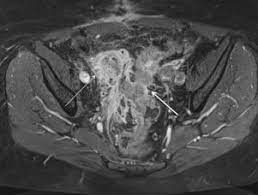

Differential Diagnosis For Female Pelvic Masses Intechopen from www.intechopen.com If my doctor had been listening to me, i would have been diagnosed at stage i instead of almost a iii more than one year later! I am 41 and went my whole life without a uti, but lat year got one that was treated, but after treatment, i still had symptoms and blood present in urine. Chait's practice interests include digestive conditions such as colon cancer, gastrointestinal endoscopy and internal medicine. The differential diagnosis of diverticulitis vs. Hi, please can anyone help me, am in so much pain. Women presenting with symptoms of ovarian cancer often receive a diagnosis of ibs, diverticulitis, urinary tract infection or changing menopausal status. 10% of women can also have ovarian cancer. dr. Spotting can be linked to several different health issues, and one of them is ovarian cancer.

This study aimed to evaluate the risk of colon diverticulitis ovarian cancer. The differential diagnosis of diverticulitis vs. However, just as the conditions have similarities, they have many differences. Could your irritable bowel syndrome (ibs) really be ovarian cancer? When a woman is diagnosed with diverticulitis the doctor should also screen for ovarian cancer.

Ovarian cancer can attach to the intestinal tract, causing symptoms that mimic irritable bowel syndrome (ibs). I had a full hysterectomy on december 12 th, and ovarian cancer stage 3 , serous, was confirmed. Many people think that the acids in their stomach are the main part of the digestive process, but the majority of digestion. Ovarian cancer is one of the most misdiagnosed diseases because its symptoms are so similar to many benign conditions. To understand about bloating, doctor oz first explained what happens every time we eat. Ibs is more common in women. This study aimed to evaluate the risk of colon diverticulitis ovarian cancer. In these sorts of situations, treatment for either condition is. When looking at endometriosis versus ovarian cancer, it is clear to see that some symptoms are shared by the two. Colon and ovarian cancer have an association in the genetic colon cancer disorder hnpcc; A ct scan showed a tumor on my left ovary. When a woman is diagnosed with diverticulitis the doctor should also screen for ovarian cancer. On the other hand, there are patients who have these diseases/disorders that have been diagnosed with colon cancer.